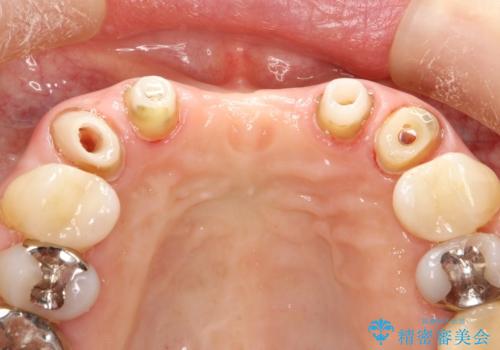

- 仮歯の製作、古い土台(メタルコア)の除去まで行い、根管治療は専門医に依頼

→根管治療終了後、ファイバーコアを築造し、新しいセラミックブリッジを製作した。

一見きれいにはいっているセラミックも、はずして中の状態をみるとひどいことが多い。これは、中の土台の状態や処理のクオリティは、短期的には問題を起こしづらく、患者さんには見えない部分だからです。